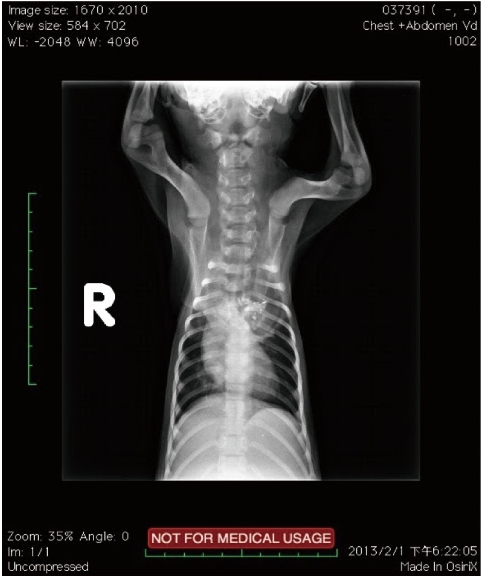

發病年齡,往往都在二到三個月大,通常都是長時間的慢性嘔吐、極度消瘦丶極度飢餓來醫院就診,x光是最好的診斷工具,除了明顕的食道擴張(心基部之前),常常可以發現吸入性肺炎的胸腔影像。

【圖十一】兩個月大的米克斯幼犬, x光下發現食道在心基部之前擴張